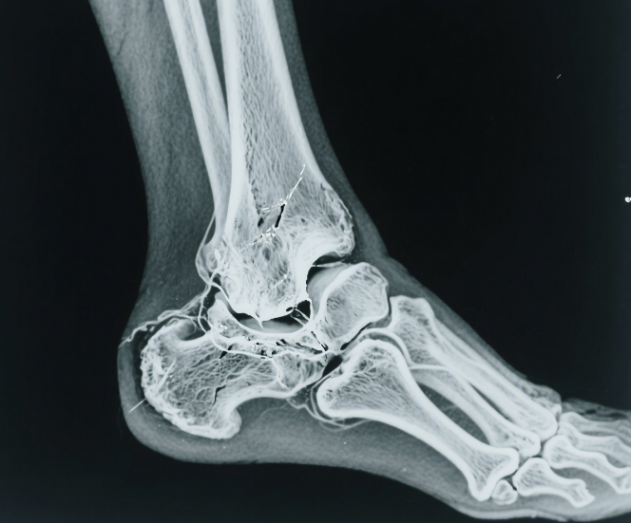

三、踝关节扭伤:看似普通,却“隐藏危机” 踝关节扭伤是高考后狂欢中最容易被低估的伤害。科学处理要遵循 RICE 原则: Rest(休息):立即停止活动 Ice(冰敷):伤后48小时内每2小时冷敷15分钟 Compression(加压):弹性绷带包扎防肿胀 Elevation(抬高):高于心脏水平 如果出现无法负重行走超过四步、踝关节骨性突起处剧烈压痛、脚部麻木或针刺感等警示信号,一定要立即就医!